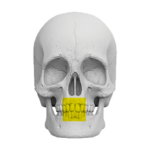

Zakres pracy tomografu.

(Badanie CBCT)

Szczęka ( 10 cm x 5 cm )

Żuchwa ( 10 cm x 5 cm )